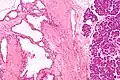

Relative incidences of various pancreatic neoplasms, with serous cystadenoma annotated near bottom right.[8]

Diagram by Mikael Häggström, M.D.